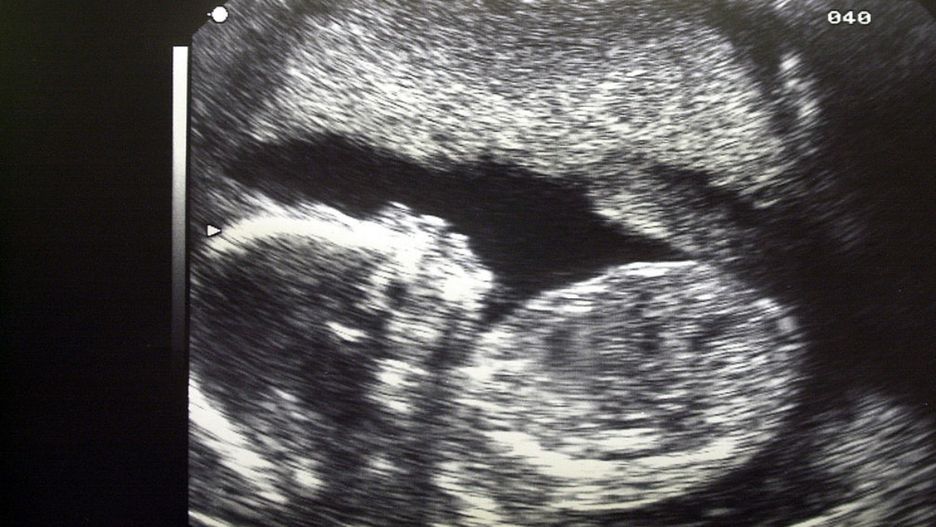

Mieszkanka Irlandii udała się w 34. tygodniu ciąży do lekarza - celem wykonania USG. Widok dziecka przeraził zarówno ją, a nawet lekarkę, która coś takiego widziała po raz pierwszym w swoim życiu. Dziewczynka miała... włosy.

USG kobiety w ciąży dziecko wlosy noworodekUSG kobiety w ciąży

Choć historia ta wydaje się niewiarygodna, to jest prawdziwa. Pewna Irlandka pokazała zdjęcie swojego dziecka, które będąc w brzuchu mamy, miało już bujną czuprynę. Jak to możliwe?

Mała Alexnadra urodziła się z włosami, co zwykle albo pokazywane jest w filmach jako fikcja literacka, albo zdarza się w 1:1 000 000 przypadków. Nie wiadomo, co odpowiada za każdy z przypadków, jednak naukowcy dopatrują się tutaj niezidentyfikowanego jeszcze genu, który pochodzić może od praprzodków danego dziecka.

Z wcześniejszych badań wiedzieliśmy już, że na świat przyjdzie dziewczynka. Chcieliśmy sprawdzić, czy dziecko rozwija się prawidłowo, a także jak bardzo urosło. Kiedy lekarka odwróciła monitor w trakcie USG, zobaczyłam główkę pokrytą gęstymi włosami. Pomyślałam, że to niemożliwe. Mówiąc zupełnie szczerze, myślałam, że wszystkie dzieci rodzą się kompletnie łyse - mówi kobieta w rozmowie z The Sun.